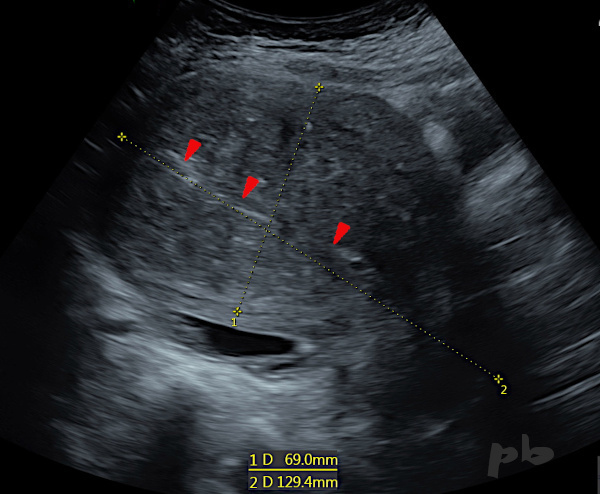

7-Adénomyose diffuse – écho voie sus-pubienne

Coupe sagittale : volumineux utérus, comme le montre ses mensurations en bas de l’image, non déformé.

Le myomètre présente un aspect hétérogène, « mité », sans image focale individualisable.

L’endomètre ( ► ) reste centré, mais est difficile à délimiter.

7-Diffuse Adenomyosis – Transabdominal Ultrasound

Sagittal section : large uterus, as shown by its measurements at the bottom of the image, not deformed.

The myometrium has a heterogeneous, ‘moth-eaten’, Swiss cheese appearance, without any identifiable focal image.

The endometrium (►) remains centered but is difficult to delineate.